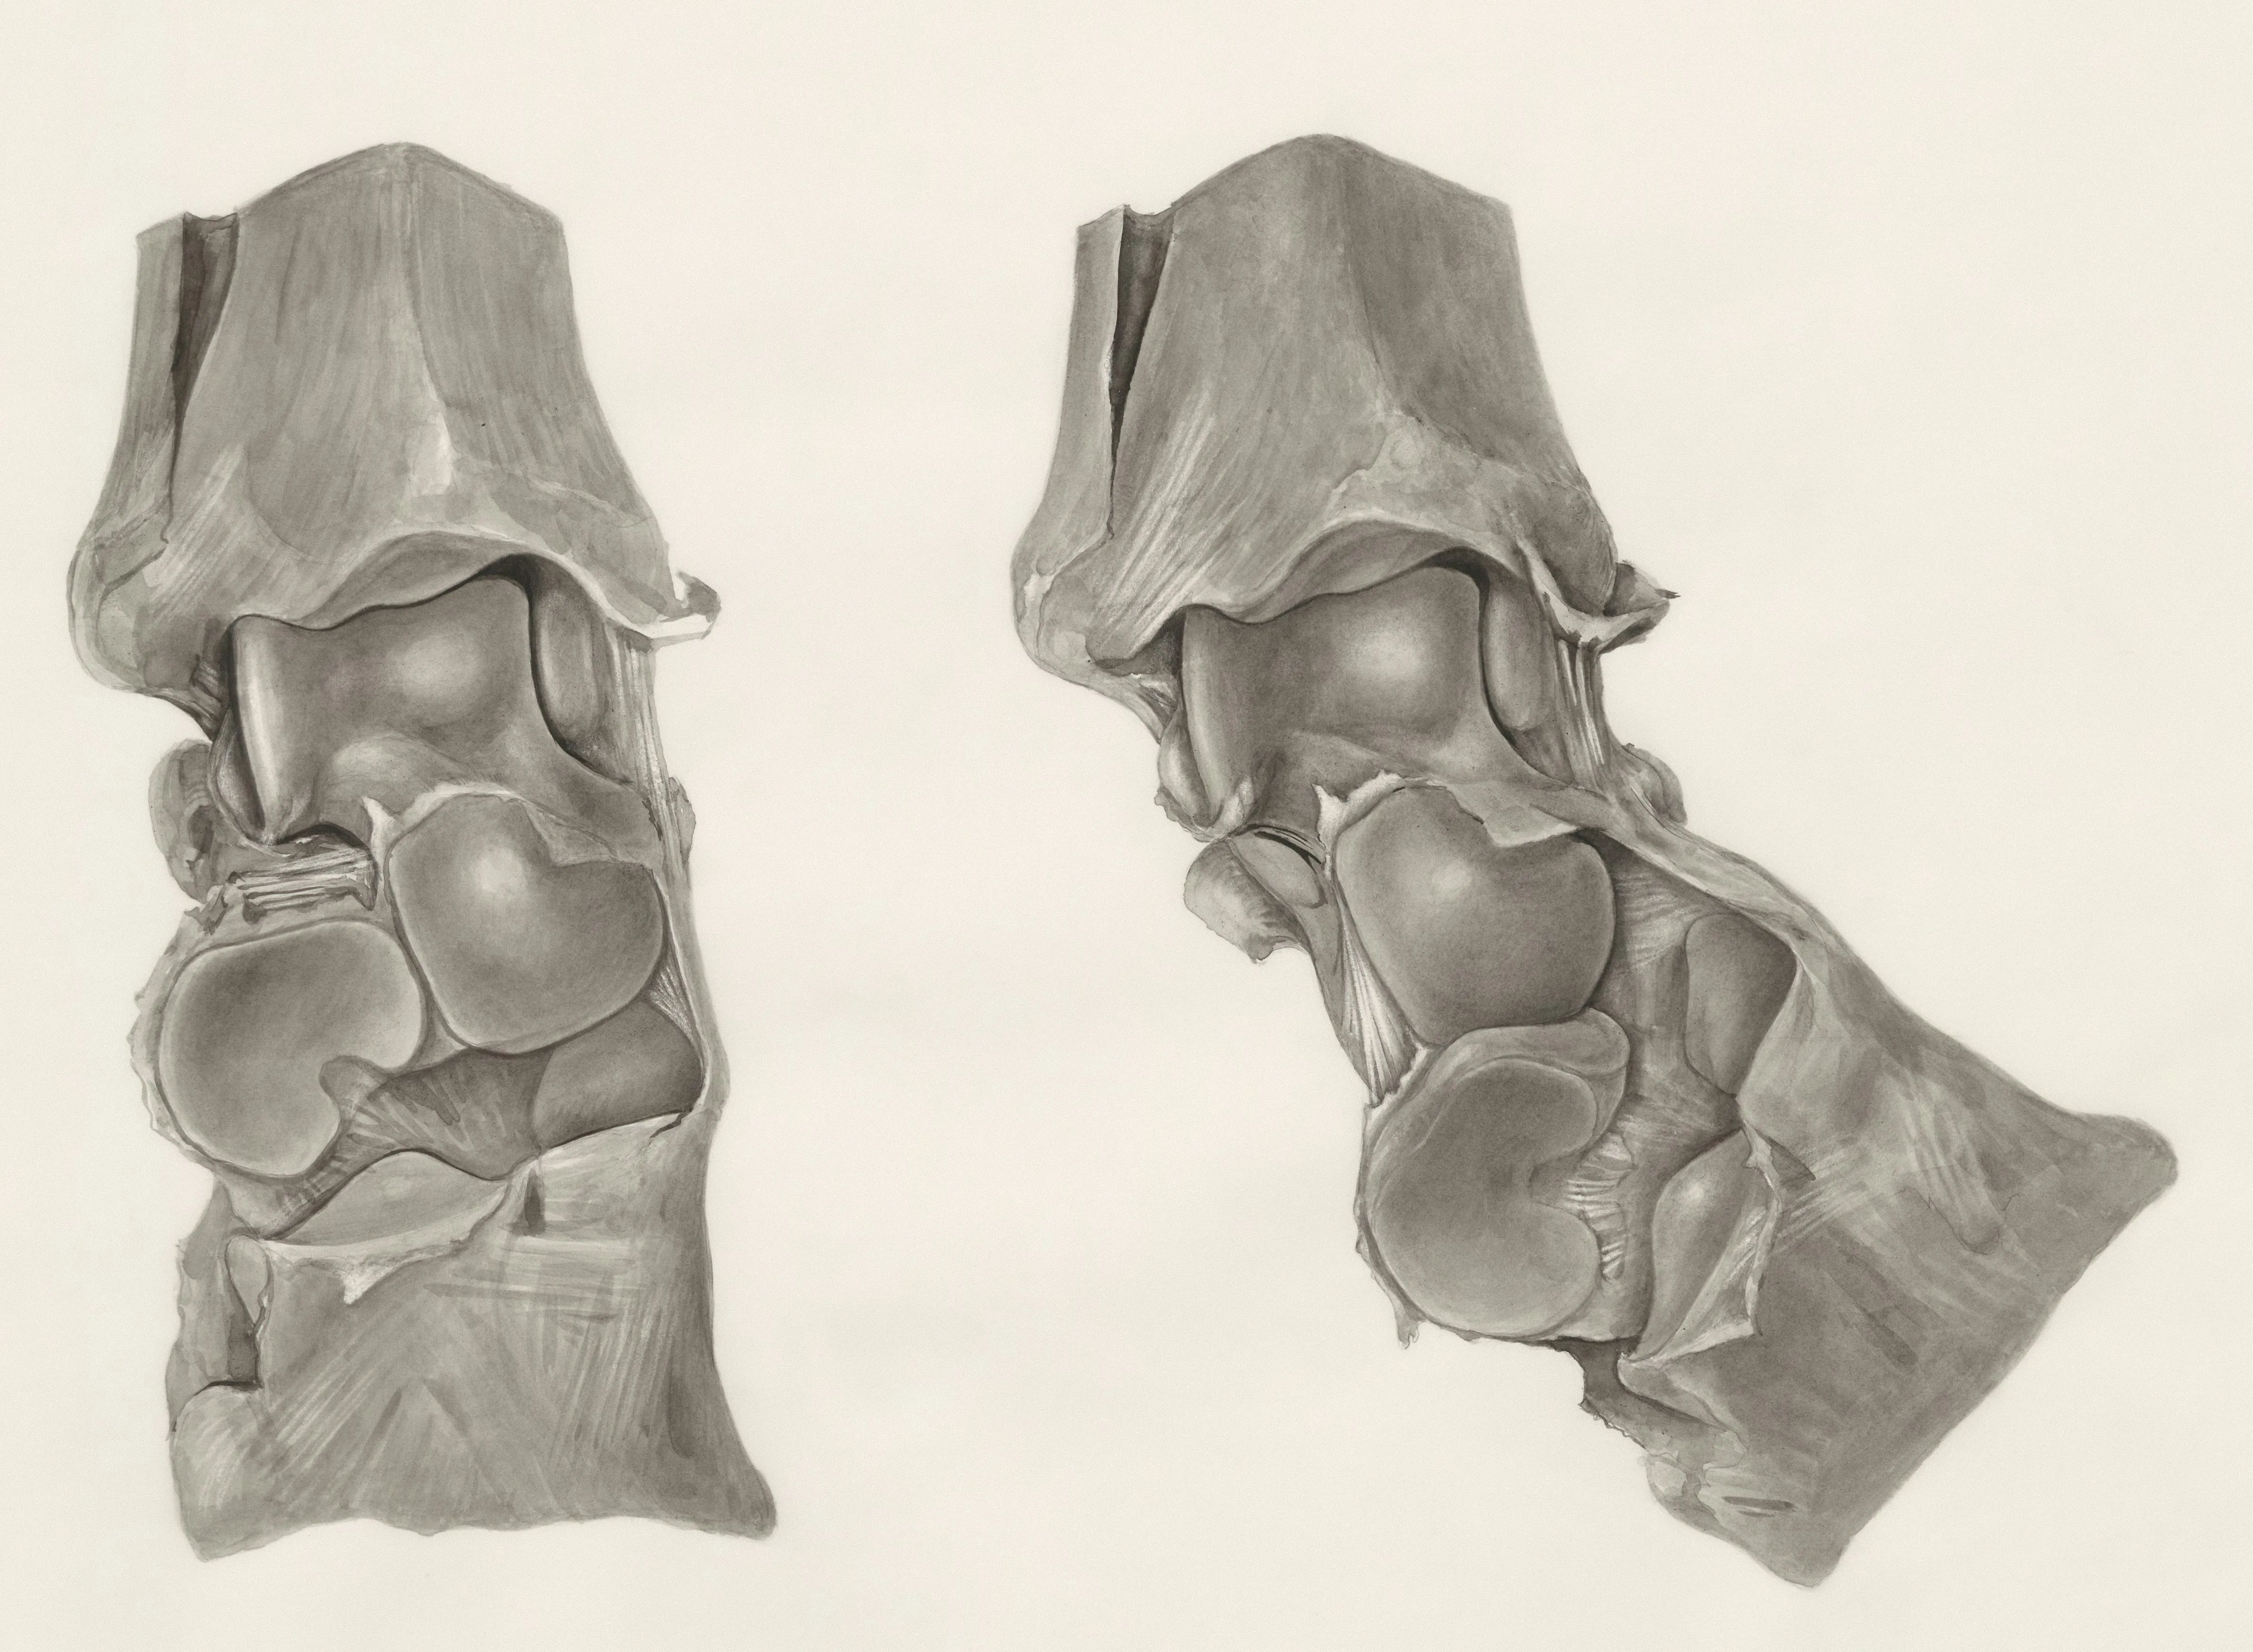

쉽게 말해, MSM은 인체의 결합 조직(관절, 인대, 연골, 피부 등)을 튼튼하게 유지해주는 역할을 하는 물질입니다.

MSM 효능 1 관절 통증 완화

MSM 효능 중 가장 대표적인 것이 바로 관절 염증 완화와 통증 감소라고 합니다.

MSM이 염증을 유발하는 사이토카인 분비를 억제해주고, 연골의 손상을 막아주는 역할을 하기 때문입니다.